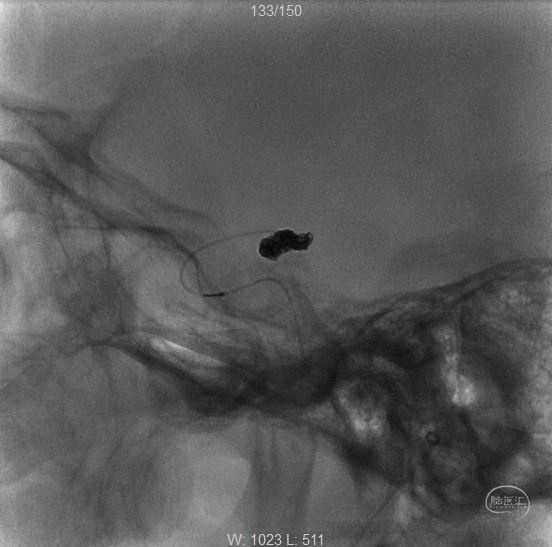

女性,66岁,突发剧烈头痛2小时。Hunt-Hess二级。

右侧颈内动脉-后交通动脉段分叶状动脉瘤。

正侧位

三维